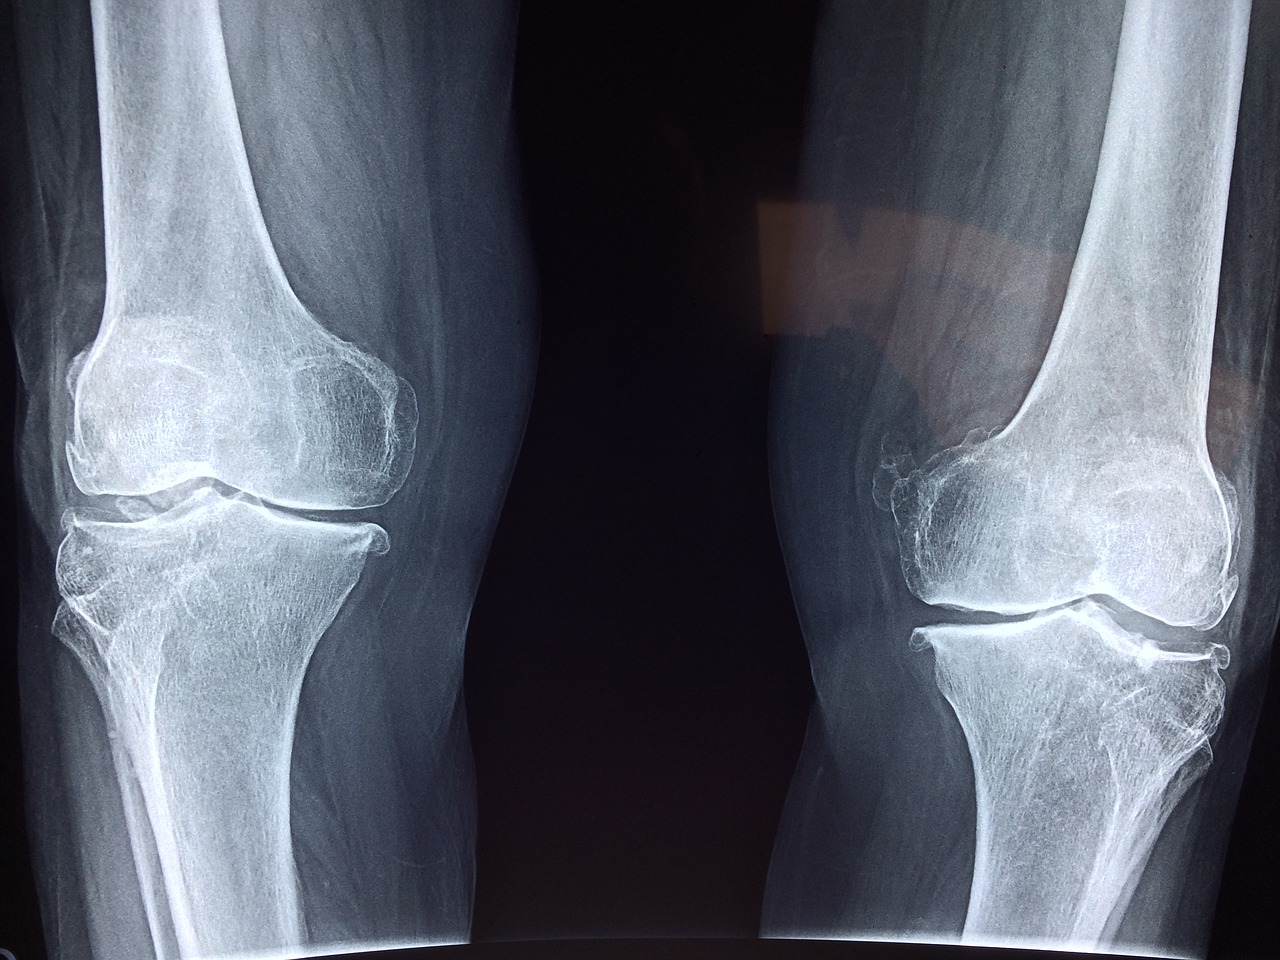

Bóle kości, stawów czy kręgosłupa potrafią bardzo uprzykrzyć życie.

Osoba ma ograniczone możliwości poruszania się, a ból może ją dosłownie sparaliżować. Nie czekaj na cud i wypróbuj tę skuteczną naturalną mieszankę, która może przynieść upragnioną ulgę.